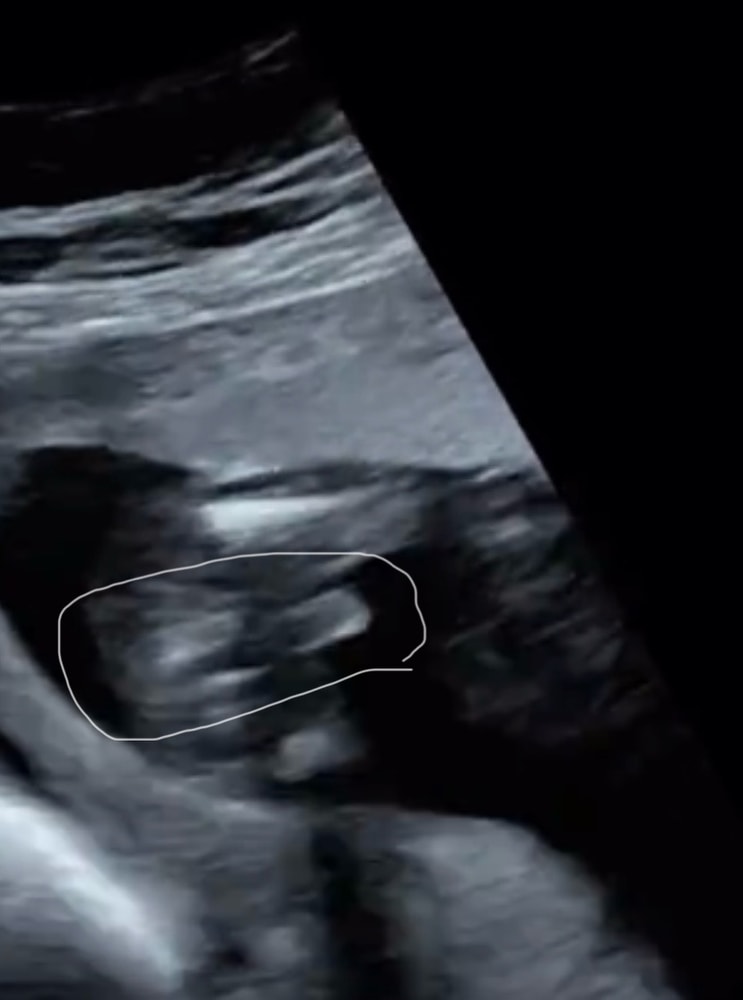

Майя , Изображение Вот похоже на ваше. Но это пуповина

12.04.2025

Алина, вот и мне показалось что похоже больше на пуповину. Посмотрим что скажут на 2 скрининге в 20 недель)